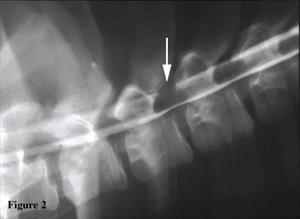

The cisternal CSF was unremarkable, while the lumbar CSF showed a mild elevation in protein (57.3 mg/dl, normal range up to 45mg/dl). A small focus of amorphous mineralization was evident on plain radiographs lying between the dorsal laminae of the third and fourth thoracic vertebrae (Figure 1).The myelogram showed mild extradural compression of the subarachnoid space at the same site (Figure 2). Based on these findings, the thoracic spine of the dog was imaged using a third generation CT scanner (GE Sytec SRI). Contiguous transverse images were acquired at one millimeter intervals parallel to the vertebral end-plates from mid body of the third through mid body of the fourth thoracic vertebrae. Scanning parameters were 120 kVp, 80mA, with a scan time of five seconds per slice. The mineralized focus noted on the plain radiographs was clearly visible extending from between the dorsal laminae of the third and fourth thoracic vertebrae into the vertebral canal via the left intervertebral foramen (Figure 3).The radiographic findings were consistent with a diagnosis of tumoral calcinosis. Since no abnormalities could be detected on palpation and orthopedic examination of all four limbs, the owner did not want to pursue diagnostic imaging of the limbs to rule out other possible foci of periarticular soft tissue mineralization.

Figure 2.

Figure 2. Myelogram of the thoracic spine. The myelogram reveals subtle narrowing of the subarachnoid space between the third and fourth thoracic vertebrae (arrow).